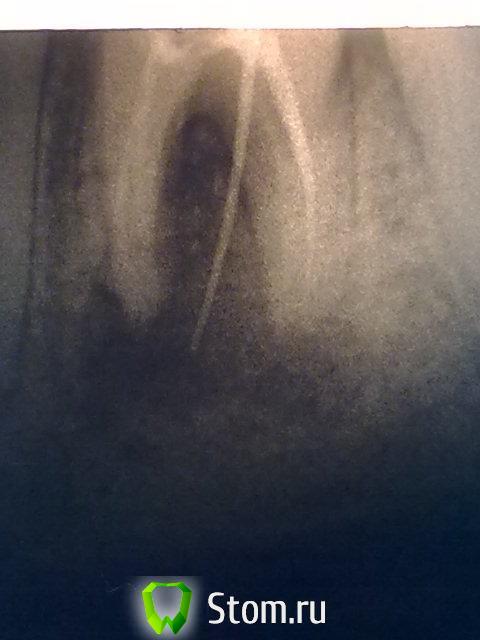

Рустам Опубликовано 14 августа, 2013 Автор Поделиться Опубликовано 14 августа, 2013 (изменено) Пришла пациентка на прием, прошло 1,5 года после того как мы пролечили ей проблемный 4.6. Лечение 4.6 было закончено 17.02.2012 г., на устья жидкотекучий, пломба "Харизма", объяснил что при положительной рентгенологической картине в динамике, будем протезировать вкв + м/к, после родов. Девушка родила мальчика, сейчас кормит грудью 2,5 мес..Можно ли сейчас приступать к протезированию? Как считаете?http://img-fotki.yandex.ru/get/9153/22303897.13/0_a23fc_4cbe6812_XL.jpghttp://fotki.yandex.ru/users/rrustam2004/view/664572/смущает небольшое разрежение в области фуркации, и кажется несостоятельность пломбы медиально, хотя во рту все бледно розовое и при зондировании все ок.Перфораций в области фуркации не было.http://img-fotki.yandex.ru/get/9489/22303897.13/0_a23fd_8ce72d3d_XL.jpghttp://fotki.yandex.ru/users/rrustam2004/view/664573/ Изменено 14 августа, 2013 пользователем Рустам 1 Ссылка на комментарий